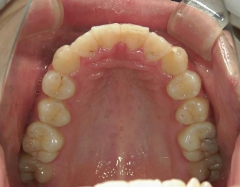

矯正歯科 治療後

矯正_灰色.pngno.6_8296_治療後_上.jpg矯正_灰色.png

no.6_8296_治療後_右.jpgno.6_8296_治療後_正面.jpgno.6_8296_治療後_左.jpg